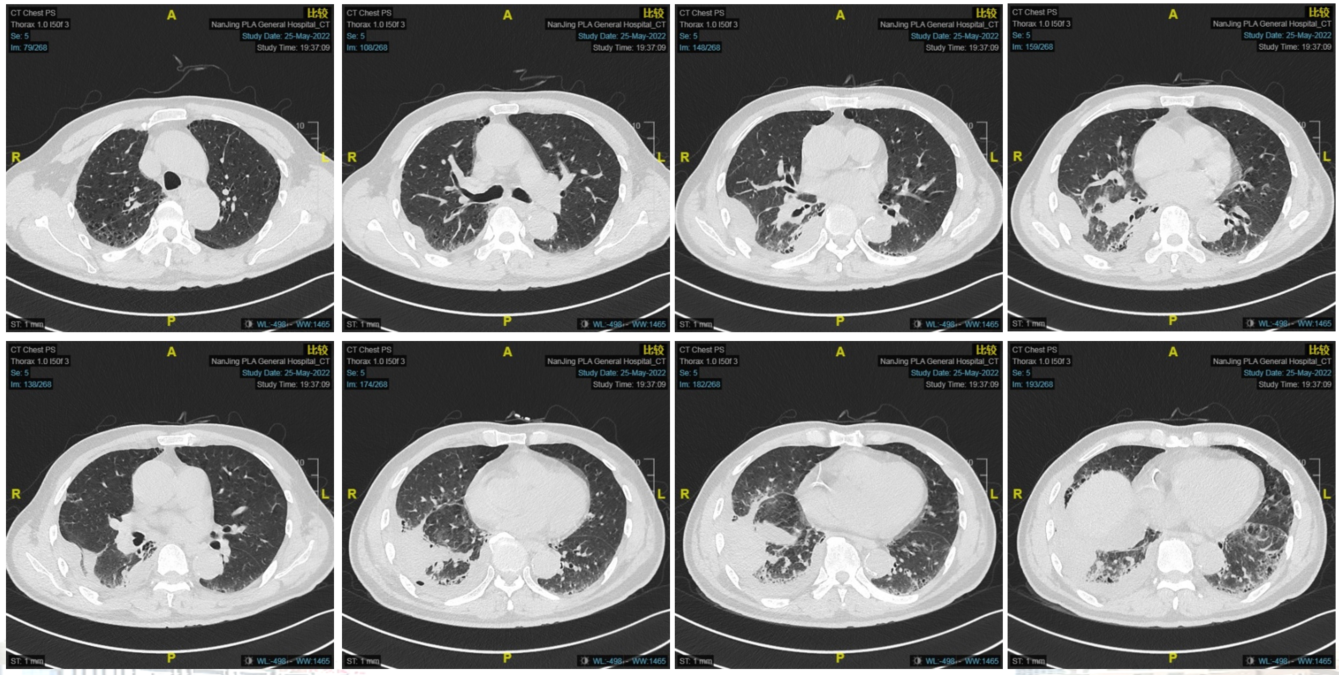

图片3.png

图3.治疗后评估

疗效评估为部分缓解(PR)。

2022-09-18完成第六周期化疗联合免疫治疗,末两次化疗紫杉醇聚合物胶束输液时皮肤过敏。

后免疫维持治疗进行中。